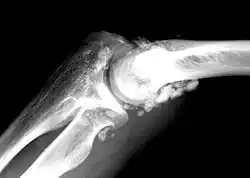

X-ray of an elbow affected by synovial chondromatosis

Synovial chondromatosis is a locally aggressive bone tumor of the cartilaginous type.[1] It consists of several hyaline cartilaginous nodules and has the potential of becoming cancerous.[1]

In the early stages of the disease it is often confused with tendinosis and/or arthritis. Once it reaches transitional the loose bodies become apparent with X-ray in greater than 70% of cases, with MRI often showing where xray fails. In experienced hands, ultrasound is also useful for the diagnosis.[2]

Rare and little known, with currently no known cure, the disease gradually forms blisters in the thin flexible membrane of the synovium, which calcify and enlarge. These nodules eventually break free and float around the joint space becoming larger – these add to the discomfort and stiffness of the joint. The affected tissue will show up as a semi-solid mass in an MRI scan, final diagnosis is usually confirmed by taking a biopsy. The disease generally affects only one of the larger weight bearing joints (hip, ankle, knee) – although the elbow, and wrist can also be affected. It rarely involves the temporomandibular joint (TMJ) and most publications are case reports.[3]